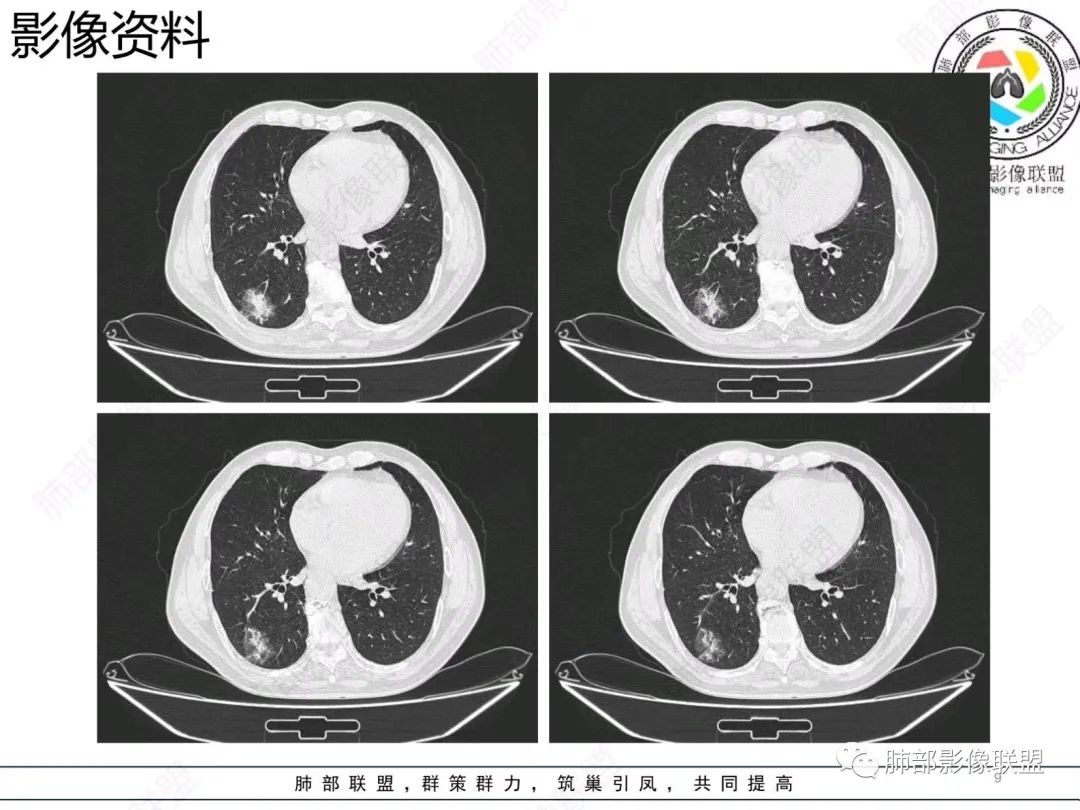

【病例】胸膜下的混合密度结节—良恶之争

老年男性,右肺下叶混合磨玻璃密度结节,可见血管弯征,首先考虑肺腺癌。

右肺下叶背段不规则结节,边界欠清,可见少许晕征,另见胸膜凹陷征及血管弯,考虑腺癌,鉴别隐球菌。

右肺下早不规则结节,周围少许磨玻璃晕,胸膜有牵拉凹陷,虽然部分边界平直,但血管受牵拉弯曲,首先还是考虑肿瘤,腺癌

右肺下叶背段斑片影,边缘平直、局部膨隆,可见磨玻璃密度影,界清,胸膜牵拉,良恶性需要进一步鉴别,倾向隐球,鉴别粘液腺癌。

老年男性,右肺下叶胸膜下结节,边缘见清晰磨玻璃密度影及少许索条,支气管进入后截断,周围血管弯,考虑腺癌,鉴别隐球菌

右肺下叶胸膜下混合密度结节,分叶、毛刺,磨玻璃边界尚清晰,血管集束,支气管进入阻断,考虑腺癌

右肺下叶背段胸膜下肿块,边缘不规则,分叶,毛刺,有磨玻璃,边界清,近肺门侧见血管聚集,支气管进入后闭塞,右肺下叶肺静脉牵拉扭曲。诊断,支持腺癌

老年患者,无呼吸道相关症状,肺部影像学表现:胸膜下占位,有结节融合趋势,内有低密度灶。考虑隐球菌,鉴别腺癌。

胸膜下结节,与胸膜平行,多结节融合,边缘模糊,直边征,考虑炎性肉芽肿,隐球,腺癌

右肺下叶背段实性结节,边缘分叶,较平直,长轴平行胸膜,胸膜增厚,考虑炎性假瘤,隐球菌,鉴别腺癌。

混合性磨玻璃结节,边界清晰,血管打弯,考虑腺癌,鉴别炎性肉芽肿病变。

老年男性,体检发现,无症状,右肺下叶背段肿块影,边缘清楚,无卫星灶,棘状突起,毛刺征,血管集支束,空泡征,考虑恶性肿瘤。

老年男性,体检发现。右肺下叶混合磨玻璃结节,渗漏征,短毛刺,血管集支束,空泡,考虑腺癌。

老年男性右肺下叶靠近胸膜一不规则混合密度影,周围有渗出,内见支气管扩张,考虑炎性病变隐球鉴别腺癌

老年男性 右肺下叶胸膜下见一团状实性病灶+边缘磨玻璃,边缘形态不规则,,局部有平直,长轴平行于胸膜面,整体收缩力偏弱,邻近胸膜面轻度增厚,纵隔窗显示病灶内可见支气管充气,考虑炎性肉芽肿,隐球菌可能,鉴别黏液腺癌。

右肺下叶实行病灶,边缘部分有边界清晰的磨玻璃影,实变明显层面,可见平直。考虑腺癌

右下肺近胸膜病变,周围可见磨玻璃影,界限无法判断清楚?模糊?。考虑右下肺占位:真菌感染?腺癌?淋巴瘤?

右肺下叶胸膜下结节,边界清楚毛玻璃,有分叶、毛刺、血管集束及胸膜增厚,考虑肉芽肿性病变,鉴别于腺癌

右肺下叶实性病灶,局部平直,考虑炎性病变,隐球菌可能

胸膜下结节,长轴与胸膜平行,边缘模糊,直边征胸膜凹陷牵拉不明显,考虑炎性肉芽肿,隐?鉴别腺癌。

右肺下叶后基底段胸膜下斑块影,边缘清楚,有平直和膨隆特点,周围清楚GGO,较模糊(似清非清,邻近见多发纯GGO结节,以肺腺泡分布,主体病灶与胸膜平行,收缩力弱,边缘见支气管充气征,首诊断炎性肉芽肿,抗炎治疗和查下隐球荚膜抗原两方面进行,另取旧片对比,与粘液腺Ca鉴别,最后经皮肺穿刺病理诊断!

上面这些征象存在炎性病变可能,我先考虑炎性病变——隐球,这样的血管弯在肺隐球菌病里也出现过。腺癌尤其是粘液腺癌也不敢排除。建议完善血隐球菌荚膜抗原、经皮肺穿刺活检等检查。

结节型粘液腺癌,具有血管弯,支气管截断,磨玻璃边界清楚等恶性征象,同时磨玻璃内部较糊,似清非清,不符合普通腺癌附壁生长特点,更像局限的粘液成分。收缩力不强,胸膜局部微积液,内部小空洞(考虑局部粘液排除形成),所以考虑结节型粘液腺癌。